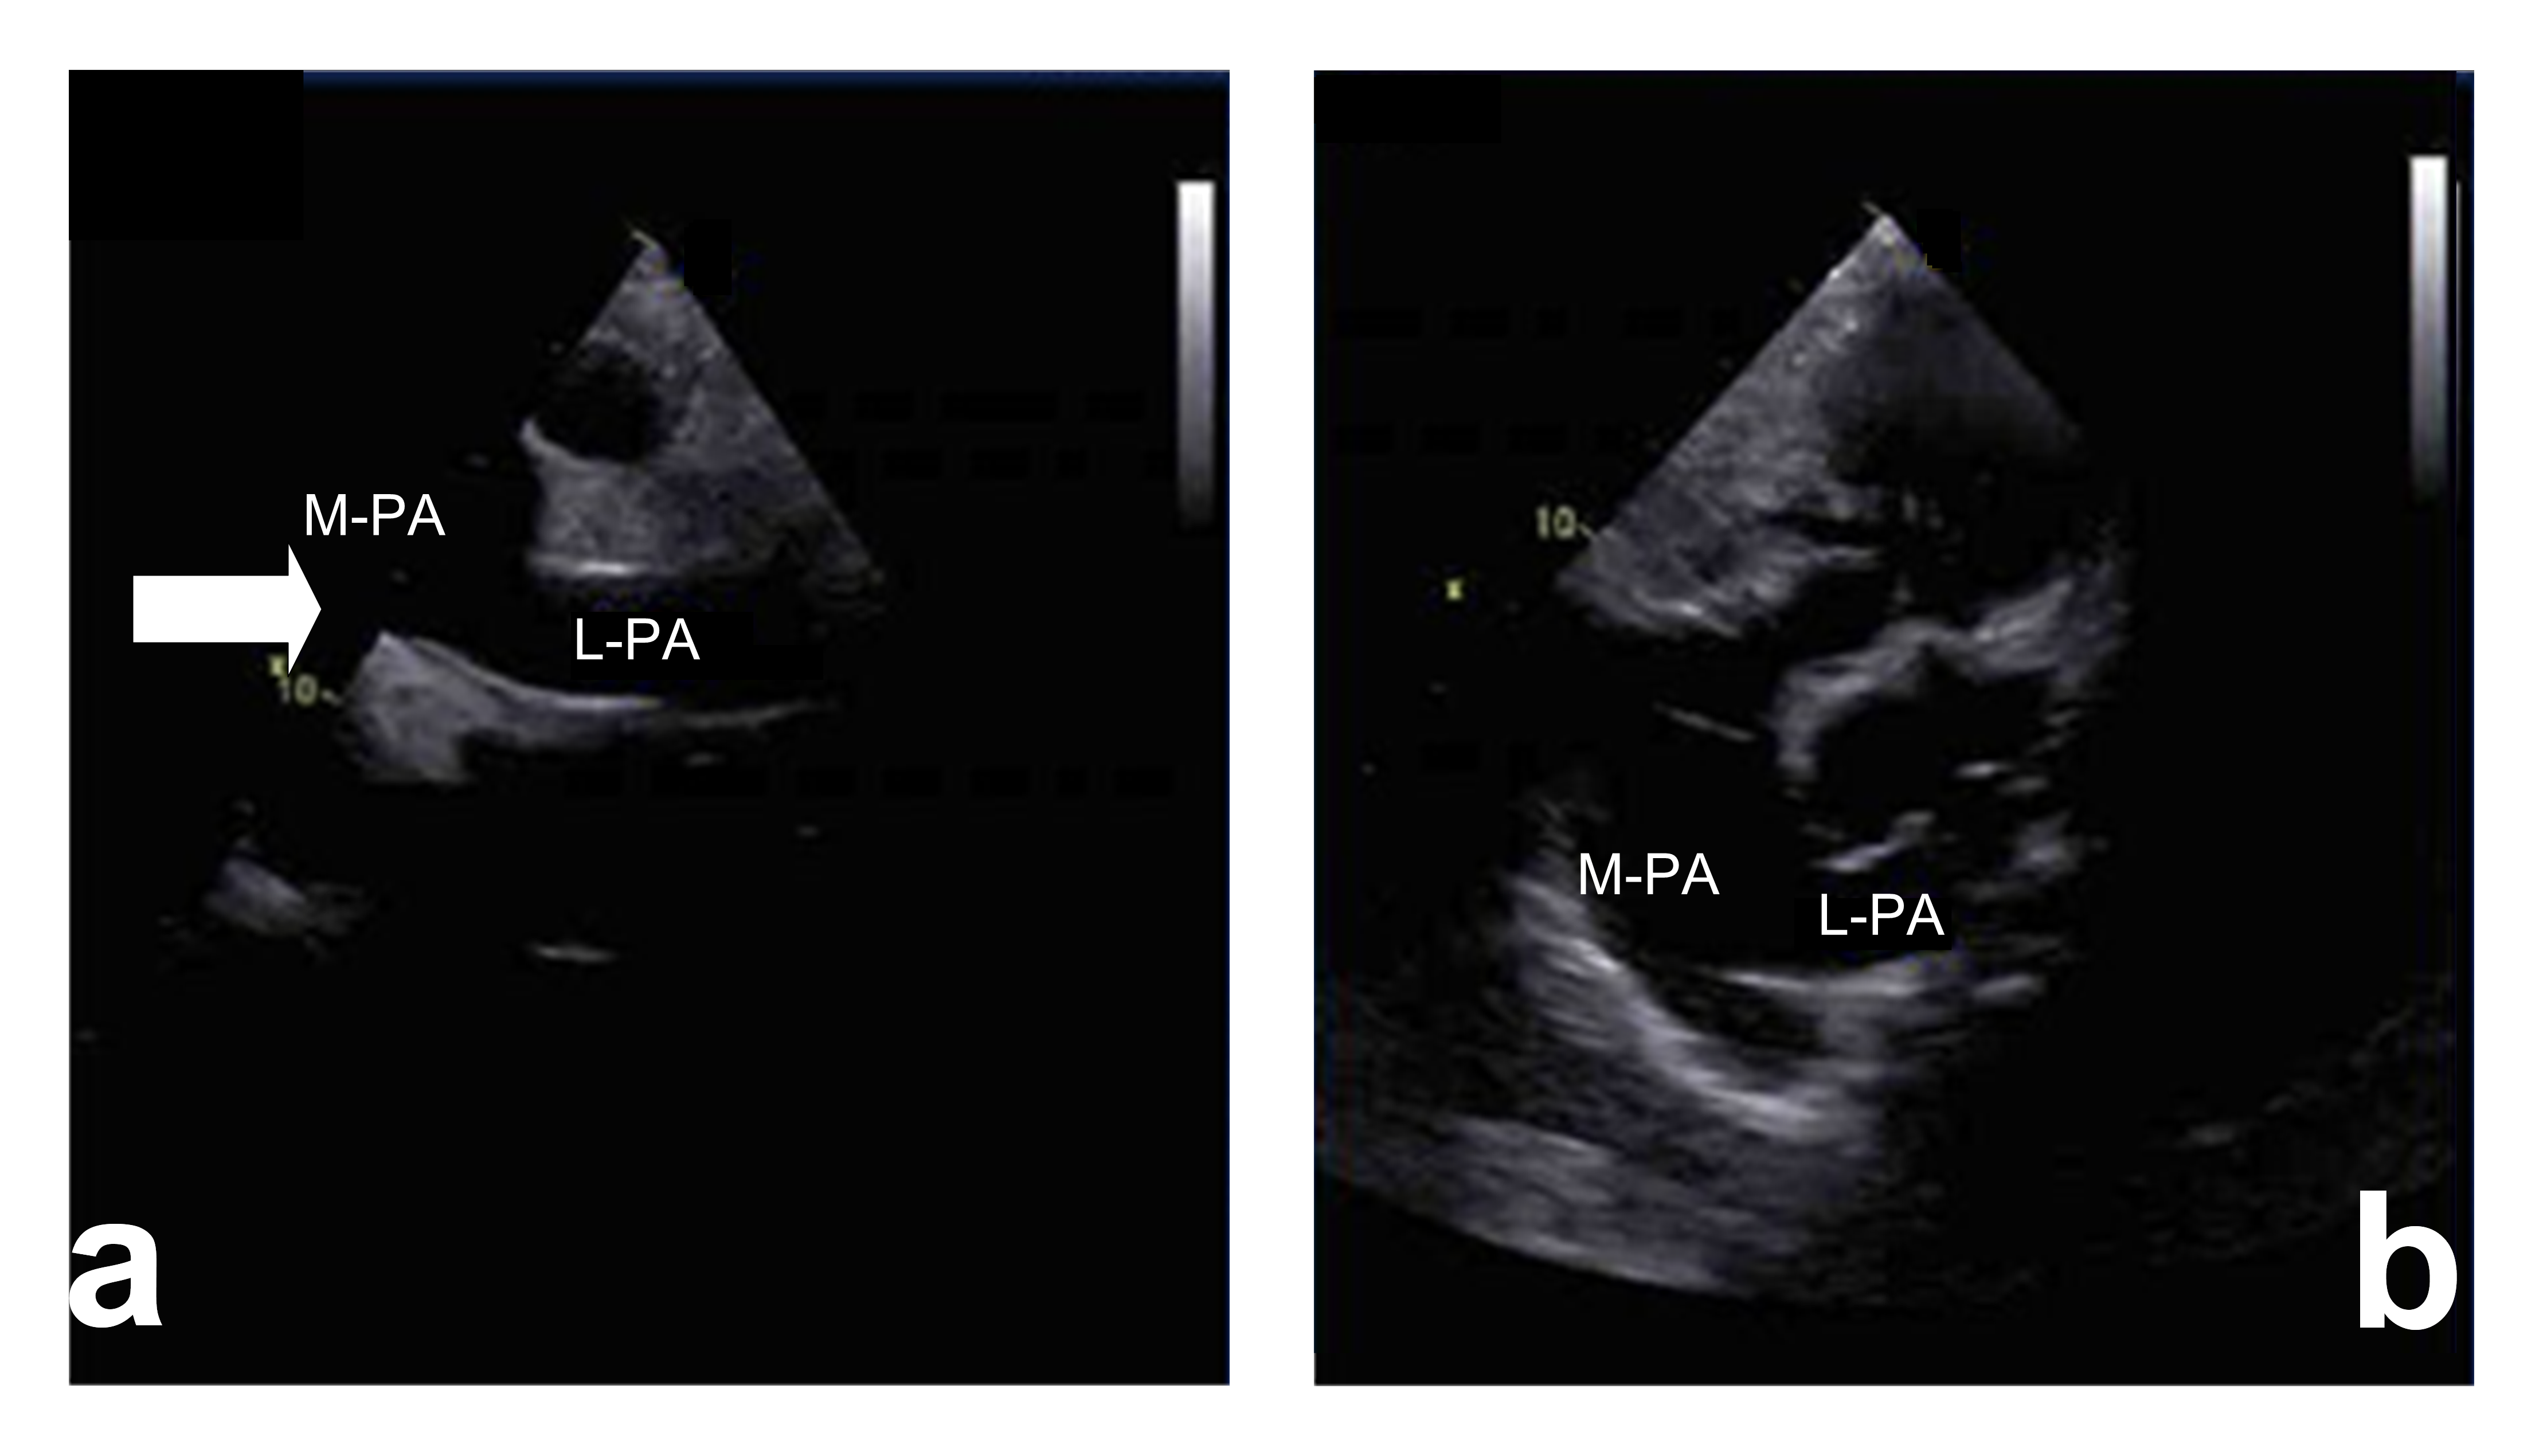

The absence of right pulmonary artery combined with single ventricle and endocardial cushion defect. There is no right pulmonary artery structure in the trunk of pulmonary artery as shown in Figs. 2,3 (hypertension group). The regurgitation peak velocity (Vmax) was 411 cm/s and pressure gradiant (PGmax) was 67 mmHg (means the mean pulmonary arterial pressure is estimated to be 67 mmHg). There is no normal ventricular septal structure in the ventricular cavity. The left and right atrium communicated with the common ventricle through the common atrioventricular valve; Combined with partial endocardial cushion defect: the normal crisscross structure between atrioventricular septum and atrioventricular valve disappear, and the echo below the atrial septum is lost.

Fig. 2.Right pulmonary artery absence with single ventricle. (a) Suprasternal long axis view (2D image). In this view there is not right pulmonary artery structure from the main pulmonary artery (arrow). LPA, left pulmonary artery. (b) High level parasternal view (2D image). In this view there is only left pulmonary artery structure from the main pulmonary artery (arrow). LPA, left pulmonary artery; MPA, Main pulmonary artery.